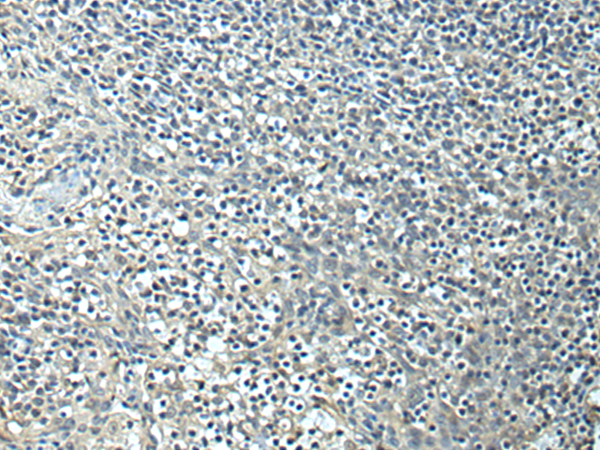

分类: 科研抗体货号: P10401别名: Gi应用: WB,IHC反应种属: Human, Mouse, Rat